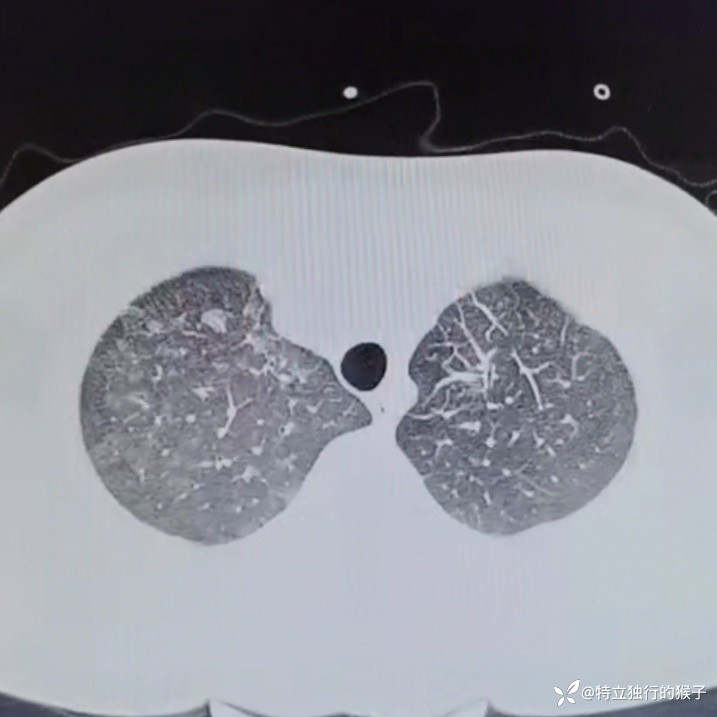

30y/M,1天前出现咳嗽,咳粉色泡沫痰,胸痛,胸闷气急,无发热。既往有肾炎病史。

查体:SpO2 85%,血压169/125mmHg,神志清,呼吸急促,口唇紫绀,两肺呼吸音粗,两肺闻及弥漫湿啰音,双下肢无水肿。

cTnI 0.66ng/ml;NT-proBNP 4183ng/ml。D-Dimer 0.17mg/l;肌酐271umol/L,BUN15mmol/L。